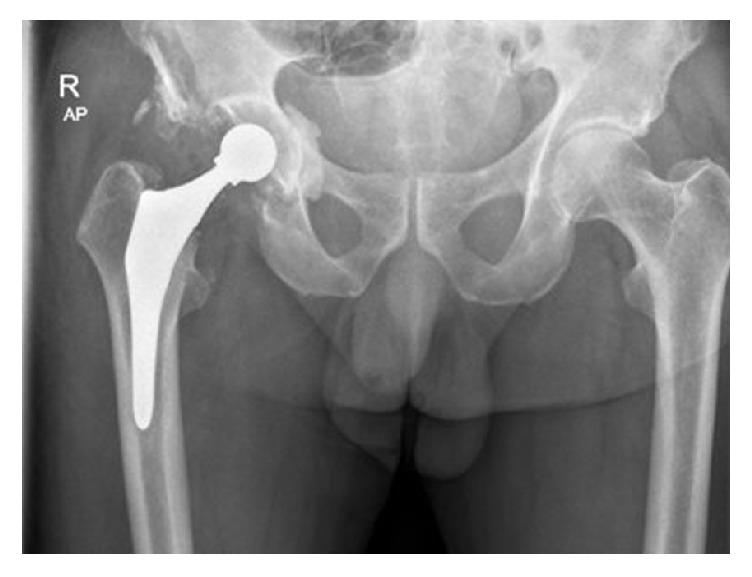

This case illustrates the potential for systemic cobalt toxicity in non-metal-on-metal bearings and its potentially devastating consequences. We present a 71-year-old male with grinding sensations in his right hip following ceramic-on-ceramic total hip arthroplasty (THA). After diagnosing a fractured ceramic liner, the hip prosthesis was revised into a metal-on-polyethylene bearing. At one year postoperatively, X-rays and MARS-MRI showed a fixed reversed hybrid THA, with periarticular densities, flattening of the femoral head component, and a pattern of periarticular metal wear debris and pseudotumor formation. Before revision could take place, the patient was admitted with the clinical picture of systemic cobalt toxicity, supported by excessively high serum cobalt and chromium levels, and ultimately died. At autopsy dilated cardiomyopathy as cause of death was hypothesized. A third body wear reaction between ceramic remnants and the metal femoral head very likely led to excessive metal wear, which contributed systemic cobalt toxicity leading to neurotoxicity and heart failure. This case emphasizes that fractured ceramic-on-ceramic bearings should be revised to ceramic-on-ceramic or ceramic-on-polyethylene bearings, but not to metal-on-polyethylene bearings. We aim to increase awareness among orthopedic surgeons for clinical clues for systemic cobalt intoxication, even when there is no metal-on-metal bearing surface.

该病例说明了在非金属对金属轴承中发生全身钴中毒的可能性及其潜在的灾难性后果。我们报告一名71岁男性,在接受陶瓷对陶瓷全髋关节置换术(THA)后右髋出现磨削感。在诊断为陶瓷内衬骨折后,将髋关节假体翻修为金属对聚乙烯轴承。术后一年,X线和MARS-MRI显示为固定的反向混合型THA,有关节周围密度、股骨头部件扁平,以及关节周围金属磨损碎片和假肿瘤形成的表现。在进行翻修之前,患者因全身钴中毒的临床表现入院,血清钴和铬水平过高支持了这一诊断,最终患者死亡。尸检推测死亡原因是扩张型心肌病。陶瓷残余物与金属股骨头之间的三体磨损反应很可能导致了过度的金属磨损,这导致了全身钴中毒,进而导致神经毒性和心力衰竭。该病例强调,陶瓷对陶瓷轴承骨折应翻修为陶瓷对陶瓷或陶瓷对聚乙烯轴承,而不应翻修为金属对聚乙烯轴承。我们旨在提高骨科医生对全身钴中毒临床线索的认识,即使不存在金属对金属轴承表面。